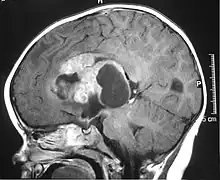

IRM d'une tumeur tératoïde rhabdoïde atypique.

La tumeur tératoïde rhabdoïde atypique (abrégé ATRT, selon l'anglais atypical teratoid rhabdoid tumor) est un type de tumeur rare, surtout diagnostiquée chez les enfants[1]. Elle se situe le plus souvent dans le cerveau, mais peut se trouver à n'importe quel autre endroit dans le système nerveux central, moelle épinière incluse[réf. souhaitée].